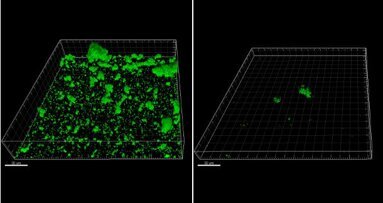

Esta abordagem contemporânea começa com remoção de biofilme sub e supragingival utilizando a tecnologia de polimento a ar AIRFLOW PLUS Powder. Este pó com base de eritritol garante a remoção do biofilme direcionada, gentil, com risco orientado, para apoiar o diagnóstico inicial. Isto é seguido por remoção minimamente invasiva do acúmulo mineralizado com PIEZON NO PAIN. Esta abordagem tem muitos benefícios adicionais, incluindo tempos de tratamento curto e máximo conforto para o técnico e o paciente.

Com GBT, finalmente podemos efetuar eficazmente a gestão profissional do biofilme, delicadamente, de forma segura, rápida e sem dor